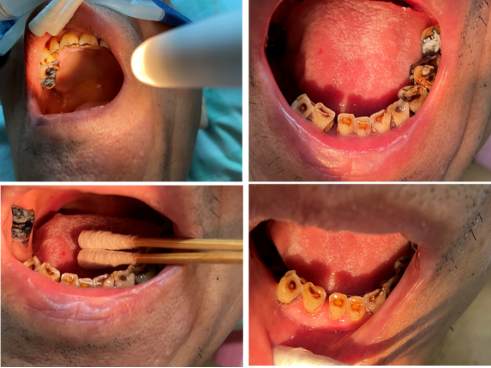

6. 感染源确认及后续治疗

追问病史,患者平素及近期有牙痛症状,检查口腔,发现较多龋齿(图6),请口腔科会诊,指导取龋齿拭子及牙菌斑标本培养,结果均发现嗜麦芽窄食单胞菌(菌落计数>15 CFU),药敏结果与血培养菌株一致,对左氧氟沙星、复方新诺明、头孢他啶、米诺环素等敏感。由此,嗜麦芽窄食单胞菌的感染源可以明确为龋齿,患者术后出现喉返神经损伤及反复误吸,肺部的嗜麦芽窄食单胞菌也可能来源于龋齿。抗感染方案为米诺环素+头孢哌酮舒巴坦联合治疗,同时予磺胺片剂溶于水漱口,建议病情稳定后口腔科专科处理龋齿。

图片

6  患者存在数颗龋齿

本例患者为老年男性,肺部手术后出现反复嗜麦芽窄食单胞菌血流感染,经多学科协作及全面排查,最终发现罕见感染源为龋齿。嗜麦芽窄食单胞菌为条件致病菌,常见感染源包括呼吸道、泌尿道、伤口及侵入性操作相关部位,龋齿作为血流感染源头的报道较少见,其可能通过破损的口腔黏膜入血引发感染。